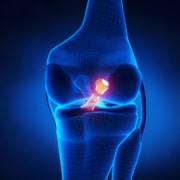

In general, Occupational Therapy is recommended for those who are hurt on the job. Some workers may receive workman’s compensation for an acute condition, while others may have experienced a lifetime of wear and tear that finally has taken its toll. A variety of examples of task- or work-related conditions include, carpal tunnel syndrome, back issues, rotator cuff injuries, thumb joint arthritis, DeQuervain’s Tenosynovitis and neck pain. Working with you, your occupational therapist will observe your work postures and habits, and will make recommendations as to how to work more efficiently by reducing strain on your body. Your occupational therapist may make recommendations as to how to make your workspace more ergonomic, or may offer certain accommodations, such as wearing protective or supportive gear or lifting less. Many times your occupational therapist will work with your employer to ensure these adaptations are in place. The goal is to create a goal-oriented plan that will restore your health and productivity, while lessening the risk of chronic pain and/or long-term injury.